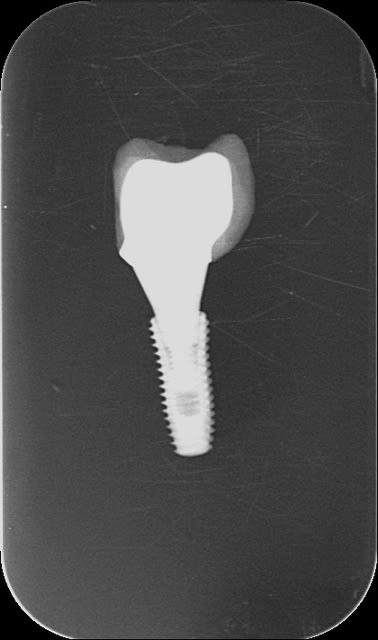

Je ne peux pas expliquer les erreurs des autres, sans avoir vu les radios.

En 3 minutes j'ai pris deux Rx (même tube, même dent même capteur, même distance) : dans un cas le pilier n'est pas vissé à fond (pas bon) dans l'autre cas il l'est (bon), note la distance entre la vis et le fond de l'implant (courte quand la vis est à fond, longue quand elle ne l'est pas ) et le hiatus clairement visible entre la cone de guidage (comme dirait Dr Marcus) et l'intrados de l'implant.

Voilà je t'ai montré, maintenant si je t'en montre 100 et qu'il y en a 10 de pas bien vissé dedans,je pense que (si les clichés sont bons et ta vue correcte) tu les retrouveras :-)

Je précise que c'est LA SEULE façon de ne pas bien le positionner, après l'autre erreur est de ne pas visser à fond ..